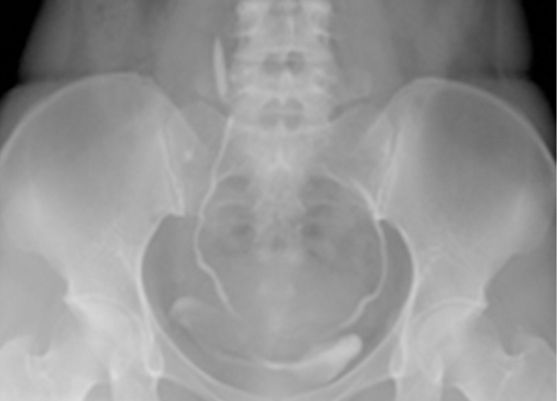

경정맥 요로조영술

단순 복부 촬영을 통해서 나타나지 않으면 시행하는 방법으로

혈관 내에 조영제를 투입하여 조영제가 신장으로 유입되어

소변이 배출될 때 함께 배출되는 원리로 이것을 활용하여

결석이 있는 부위에서 조영제가 더는 하방으로

내려가지 못하는 모습을 보고 판단을 하는 방법입니다.